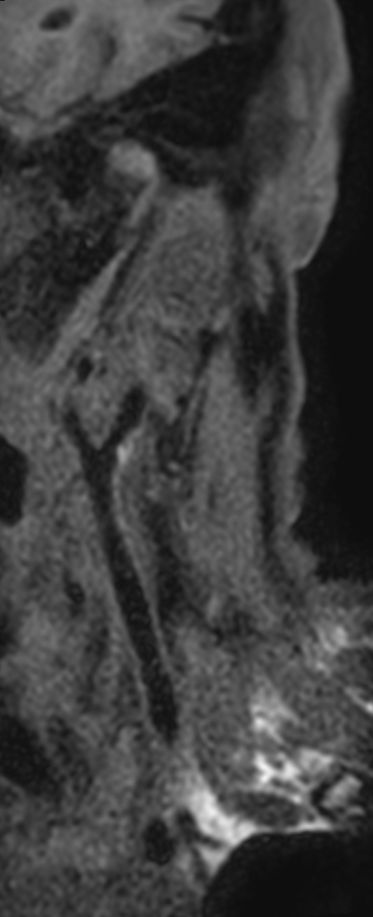

Patient with a neck stenosis. Compressed SENSE is used to shorten the total exam time.

3D T1w TSE Black Blood - Compressed SENSE